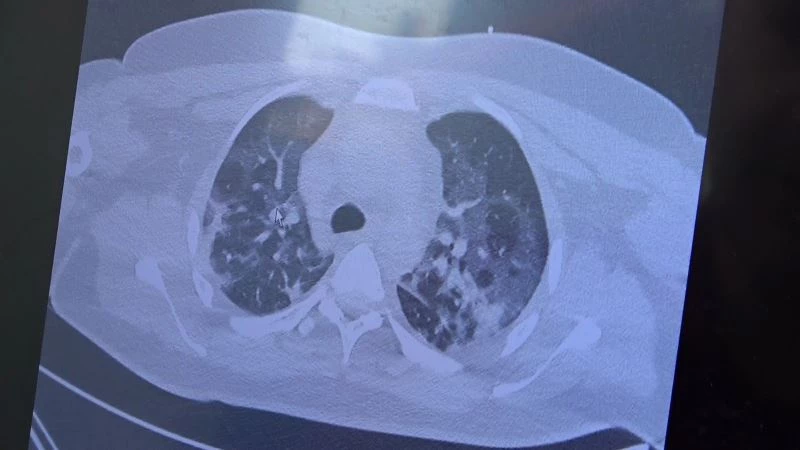

Gençlerin akciğer tomografilerini inceleyen Özkaya, "İki vaka örneği hakkında bilgi vermek istiyorum. İnsanlara bu işin bitmediğini anlatmamız lazım. 30 yaşında aşı olmamış bir hastamızın filminde çok yaygın akciğer hasarı var. Şu an kendisi yoğun bakımda tedavi alıyor. Öte yandan 25 yaşında bir hastamız var. İki doz kovid aşısını da olmamış. Ciddi akciğer tutulumları var. Çok ciddi solunum sıkıntısı ile kovid servisinde yatıyor. Şu an hasta profilimizin büyük bir kısmını bu durum oluşturuyor” ifadelerini kullandı.